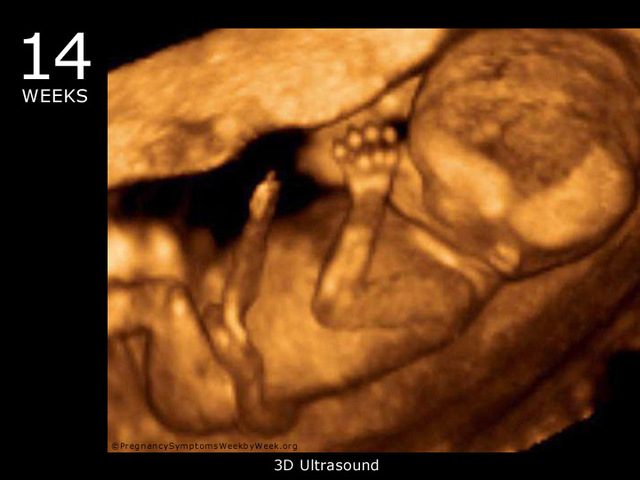

• Begins to Grow Hair (week 14)

Begins to Grow Hair (week 14)

Even though the baby's skin is thin and transparent, tiny hairs begin to grow.